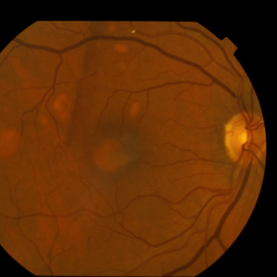

This 68 year old man was referred with a maculopathy but with normal visual acuity. He is thought to have multifocal Best Disease; there is no evidence of inflammation or uveitis and no history of cancer. Macular exam reveals yellow subretinal pigment clumping in each macula, including the foveal area. OCT shows moderate hyper-reflective PED, with no evidence of subretinal fluid or macular edema. Angiography reveals blocking defects due to pigment clumping with no evidence of CNVM.

Multifocal Best Disease Multifocal Best DiseaseJan 31 2015 by Thomas A. Ciulla, MD, MBA, FASRS Macular exam reveals yellow subretinal pigment clumping in each macula, including the foveal area. Photographer: Charlotte Harris Condition/keywords: adult vitelliform dystrophy, Best disease